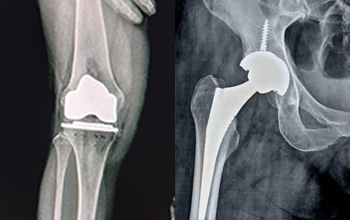

At CZMEDITECH, we are dedicated to providing reliable orthopedic solutions through real clinical success. Each surgical case reflects our continuous innovation in spinal fixation, trauma management, joint reconstruction, maxillofacial repair, and veterinary orthopedics. By integrating advanced manufacturing technology with the expertise of experienced surgeons, we ensure every implant delivers safety, precision, and long-term recovery.

Explore below a selection of clinical cases that demonstrate how our CE-certified implants help restore mobility, stability, and confidence in patients worldwide.